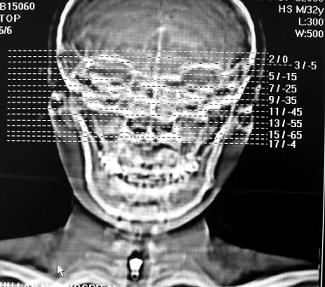

标题: CT10521:男。32岁,副鼻窦ct,请会诊。 [打印本页]

标题: CT10521:男。32岁,副鼻窦ct,请会诊。

男。32岁,鼻塞,流涕一年余。